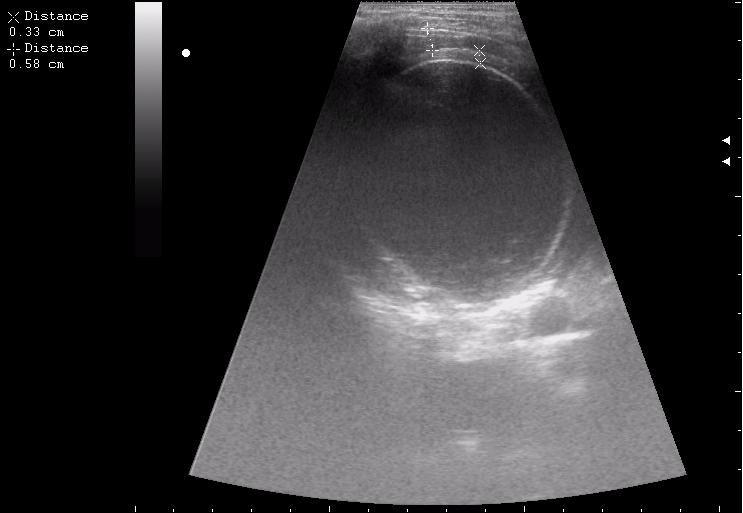

живой эхинококк.